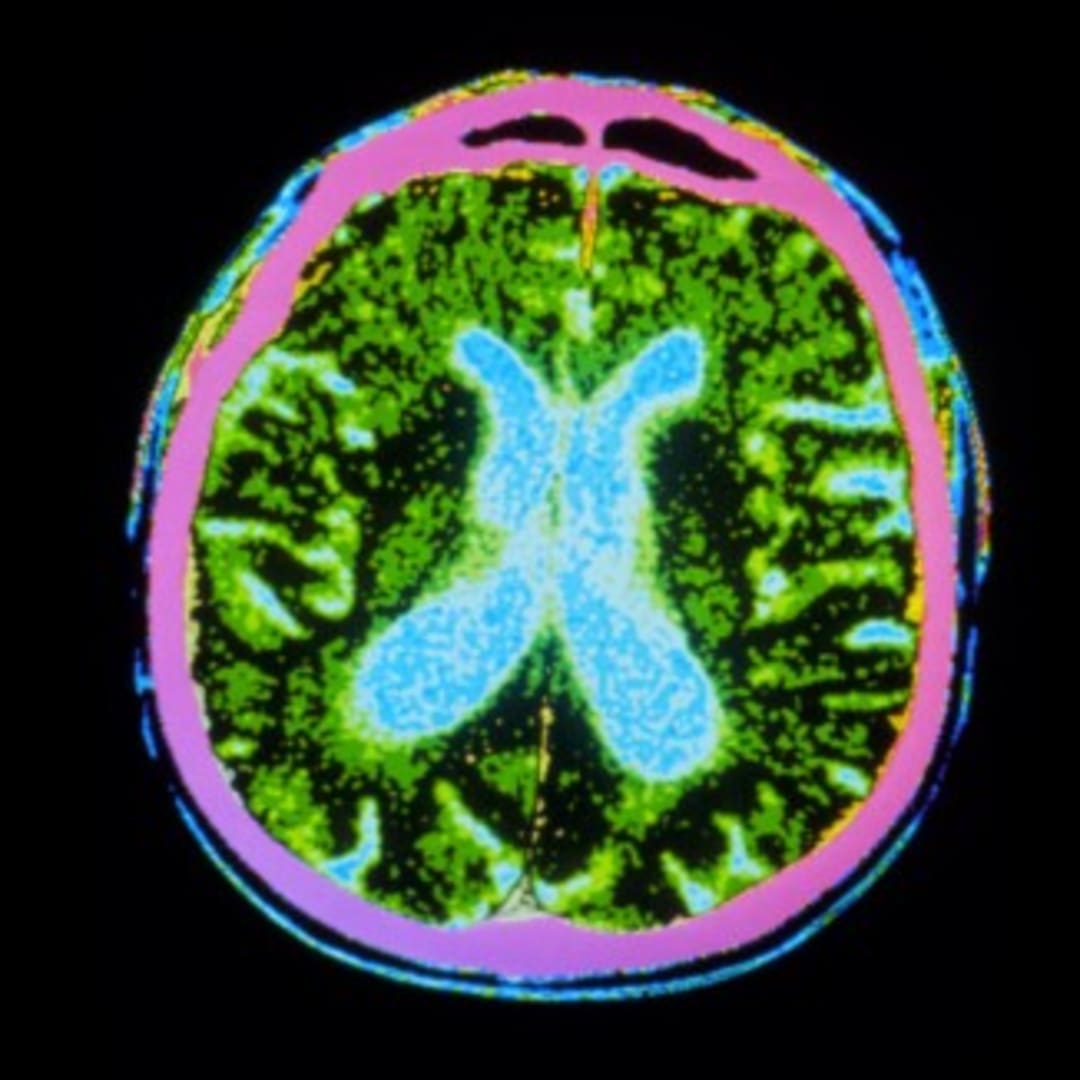

Courtesy of NatureMagazine

Penyakit Parkinson adalah kondisi neurologis progresif yang disebabkan oleh hilangnya neuron penghasil dopamin, yang menyebabkan tremor, kekakuan, dan kelambatan gerakan. Tidak ada obat untuk kondisi ini, yang diproyeksikan akan mempengaruhi 25 juta orang secara global pada tahun 2050. Terapi sel dirancang untuk menggantikan neuron yang rusak, tetapi uji coba sebelumnya menggunakan transplantasi jaringan janin memberikan hasil yang beragam.